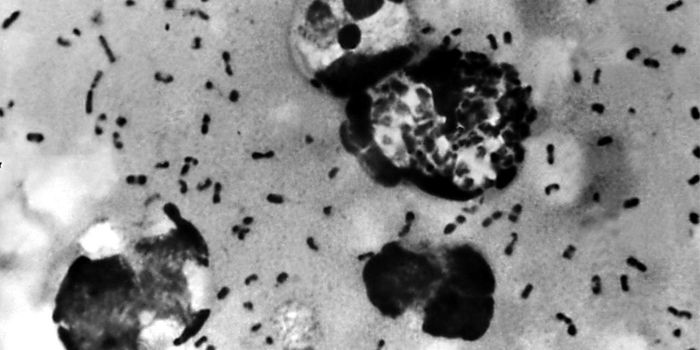

SEP 19, 2016ImmunologyYersinia pestis, the bacterial species responsible for numerous and deadly outbreaks of plague throughout human history, ...

For a new stu ...DEC 01, 2020ImmunologyThanks to a new hydrogel biomaterial developed by researchers at Duke University, we are one step closer to the holy gra ...NOV 10, 2016ImmunologyTwo proteins serve as internal clocks for immune cells, a new system of regulation that defies most of what scientists t ...DEC 17, 2020ImmunologyCanadian researchers have made a breakthrough for children with peanut allergies: immunotherapy that when taken daily fo ...JUN 23, 2016Health & MedicineFor unknown reasons, T lymphocytes are known to go rogue, leaving the bloodstream to attack the myelin sheath, the insul ...AUG 28, 2018Drug Discovery & DevelopmentAccording to a research study led by UCLA, a bacteria-like agent used in combination with an immunotherapeutic drug may ...FEB 18, 2017CancerUsing small-molecule sugars, scientists successfully made artificial tags for cancer cells that otherwise blended in wit ...AUG 20, 2018ImmunologyThe Langerhans cells of the immune system activate cytokines essential for skin protection when exposed to UV that is fu ...APR 28, 2018CardiologyWe’ve heard that dark chocolate is good for us in reasonable amounts, but two unique studies from the Loma Linda U ...JUL 28, 2022Clinical & Molecular DXFreeze drying, lyophilization, and cryodesiccation are all terms used to describe the process of removing water from a s ...NOV 10, 2020ImmunologyIn the middle of 2020, yet another deadly Ebola outbreak was reported in the Democratic Republic of the Congo - the 11th ...MAY 10, 2022ImmunologyImmunotherapies, which boost a patient's immune system so it's better at fighting cancer, have been a game-chang ...NOV 20, 2022ImmunologyGerman scientists provided a case study of a 51-year-old patient that highlighted one of the first symptoms a monkeypox- ...APR 13, 2021ImmunologyIn a recent study, researchers discovered that a fungus present in cheese, processed meats, beer, and other fermented fo ...JAN 25, 2017ImmunologyThe immune system pulls out all the stops to try and prevent cancer cells from replicating and moving throughout ...MAY 01, 2017ImmunologyCorneal transplants can be especially risky for some patients, when steroids intended to suppress the immune system fail ...JAN 30, 2025ImmunologySince the inauguration of President Donald Trump on January 20th, 2025, he has signed many executive orders, changing po ...NOV 18, 2021ImmunologyPregnant mothers pass on oxygen and nutrients to their developing babies while shuttling away waste products from the fe ...APR 02, 2020ImmunologyThe coronavirus pandemic caused by SARS-CoV-2 is demanding the world's immediate attention.OCT 23, 2016ImmunologyWhat is it about dust mites that make them such a strong allergen for so many people? Scientists from Duke University an ...FEB 29, 2016ImmunologyScientists have discovered a way to make a nasal spray flu vaccine safer for those who are at greatest risk of catching ...JUN 01, 2022Clinical & Molecular DXCancer vaccines have been around for decades, but a unique neoantigen vaccine called NeoVax is making researchers hopefu ...MAR 04, 2019Cell & Molecular BiologySleep is vital to good health for a variety of reasons. For example, the risk of heart disease increases when people don ...MAR 11, 2024Clinical & Molecular DXOnce dismissed by many clinicians, it is now estimated that as much as six percent of the world's population has fib ...JUN 22, 2016ImmunologyFindings from a new research study might convince you to feed your gut microbiota a little better. The population of &ld ...DEC 09, 2018ImmunologyWe've cured cancer and autoimmune disease in mice many times over.JUL 07, 2017ImmunologyThanks to regulatory T cells (Tregs), the immune system is kept in line via a careful system of checks and balanc ...SEP 26, 2023ImmunologyPublished by Beata Boczkowska, Ph.D. Understanding how major histocompatibility complex class (MHC) molecules ...AUG 26, 2016ImmunologyWhen four children from Pakistani and Turkish families presented with skin rashes and inflamed joints that doctors could ...MAR 23, 2021ImmunologyIt is estimated that around one in five people infected with SARS-CoV-2 will not show any infection symptoms. Some of th ...FEB 23, 2021ImmunologyUniversity of Limerick researchers have discovered direct links between the immune system, specific personality traits, ...FEB 21, 2016ImmunologyGlobal concerns about Zika virus aren’t stopping Americans from making international travel plans, but many who do ...MAR 17, 2022Drug Discovery & DevelopmentResearchers at the Ohio State University College of Medicine have created a vaccine using CRISPR technology targeting Le ...OCT 07, 2014ImmunologyThe case of the man who left Liberia and was diagnosed with Ebola in Dallas is confounding in every way, a cascade of Mu ...FEB 24, 2017MicrobiologyResearchers from Harvard Medical School have reported on the results of a large-scale search for immunomodulatory organi ...JUN 28, 2018ImmunologyThe highly complex structure and function of human T cells made the creation of synthetic versions of the immune cells d ...DEC 14, 2021ImmunologyThe eyes may be the windows to the soul, but they are also vulnerable access points for environmental pathogens. What&rs ...NOV 04, 2021ImmunologyAn increasing number of COVID-19 patients have reported ear-related issues: ringing in the ear, hearing loss, and balanc ...JUL 17, 2014NeuroscienceAs the population ages, victims of Alzheimer's disease (AD) are growing in number at a very fast rate. It's estimated th ...APR 15, 2016Health & MedicineAfter completing intense exercise, over three thousand human genes are expressed to help the body recuperate. However, d ...APR 07, 2020ImmunologyExcessive salt intake is associated with health consequences for more than just cardiovascular status; the immune system ...NOV 04, 2020Health & MedicineCOVID-19, the illness caused by the pandemic virus SARS-CoV-2, is known to cause blood clots all over the body in some p ...OCT 19, 2019NeuroscienceUntil now, diagnosis for autism spectrum disorder have relied on behavioral assessments looking for symptoms including p ...AUG 08, 2018ImmunologyChemotherapy drug Doxorubicin disrupts metabolism that controls immune responses in the heart leading to heart toxicity.JUL 21, 2014ImmunologyNew research from the University of Pennsylvania School of Nursing, published in the current issue of JAMA Pediatrics, i ...JAN 21, 2016ImmunologyHow exactly does our immune system “remember” certain pathogens so the response to an infection is more powe ...JUL 14, 2020ImmunologyScientists are working on developing an arsenal of nano-sized weapons in the war against COVID-19. These molecules, call ...JAN 20, 2022ImmunologyScientists studying a neglected tropical disease have made a chance discovery—a promising therapeutic targe ...FEB 25, 2021ImmunologyMost organ systems are protected by a cavalry of immune cells present in the circulation—but not the brain. Consid ...AUG 05, 2021ImmunologyTalking, singing, coughing—all of these can spread COVID-19 from an infected person via respiratory aerosols. Thes ...OCT 01, 2018ImmunologyThe immune system consists of a variety of different cell types. But how do the cells undergo differentiation? A study r ...MAY 04, 2021ImmunologyThere are currently five variants of concern in the U.S., genetically distinct forms of the COVID-causing coronavirus th ...FEB 09, 2018ImmunologyIt is the immune system’s duty to distinguish helpful bacteria from harmful bacteria. Thanks to millions of years ...JAN 19, 2016CancerPackaging a cancer drug in bubble containers derived from a patient’s own immune system makes it much more ef ...MAY 20, 2021ImmunologyA new study indicates that delaying the second “booster” dose of the Pfizer-BioNTech COVID vaccine (to 11-12 ...DEC 12, 2014Cell & Molecular BiologyScalloped and Yorkie genes found to be role players